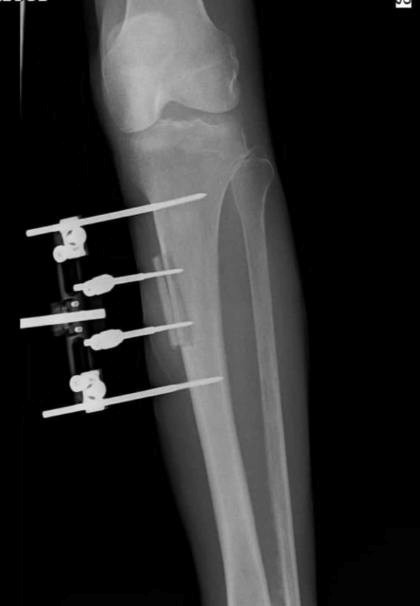

Prešovskí ortopédi zaviedli metódu TTT. (Zdroj: FNsP Prešov)

Metóda TTT využíva špeciálny externý fixátor, pomocou ktorého lekári počas niekoľkých týždňov kontrolovane transportujú tibiálny kostný blok, čím sa aktivujú obnovujúce a uzdravujúce procesy v tele pacienta. Dochádza k tvorbe rastových faktorov, podpore tvorby nových ciev, tkanív a k zlepšeniu prekrvenia, čím sa vytvárajú podmienky na hojenie. Nový liečebný postup je určený najmä pacientom s defektmi v oblasti chodidla a predkolenia, napríklad pri diabetickej nohe (komplikácia spojená s cukrovkou), poruchách prekrvenia dolných končatín, pri chronických infekciách alebo po predchádzajúcich neúspešných chirurgických výkonoch na chodidle.

„Jemnou technikou bez poškodenia priľahlých mäkkých tkanív vysekneme časť kosti, ktorú následne vysúvame z jej kostného lôžka. Vytvárame tak priestor pre tvorbu buniek, ktoré umožnia hojenie poškodeného tkaniva. Dôležité je aj to, že pod miestom osteotómie, teda kostného transportu, sa postupne vytvárajú nové cievy, čo je ďalším predpokladom úspešného hojenia. Výsledkom je, že u pacientov, ktorým hrozila strata končatiny, dokážeme vytvoriť podmienky na jej zachovanie,“ vysvetľuje MUDr. Boris Džula, MPH, primár Oddelenia ortopédie FNsP J. A. Reimana Prešov.

Metóda TTT je riešením pre presne vybranú skupinu pacientov. (Zdroj: FNsP Prešov)